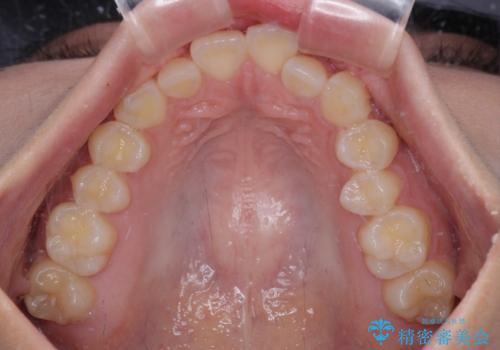

- デコボコを気にして来院された患者様です。

インビザラインでもワイヤー装置でも対応可能でしたが、自己管理の煩わしさの観点から、楽して治療のできるワイヤー装置を選択されました。

抜歯するほどではないものの、やや口元の突出感が気になっていたので、補助装置により上顎臼歯を後方に移動させることで、突出感改善を図ることとしました。